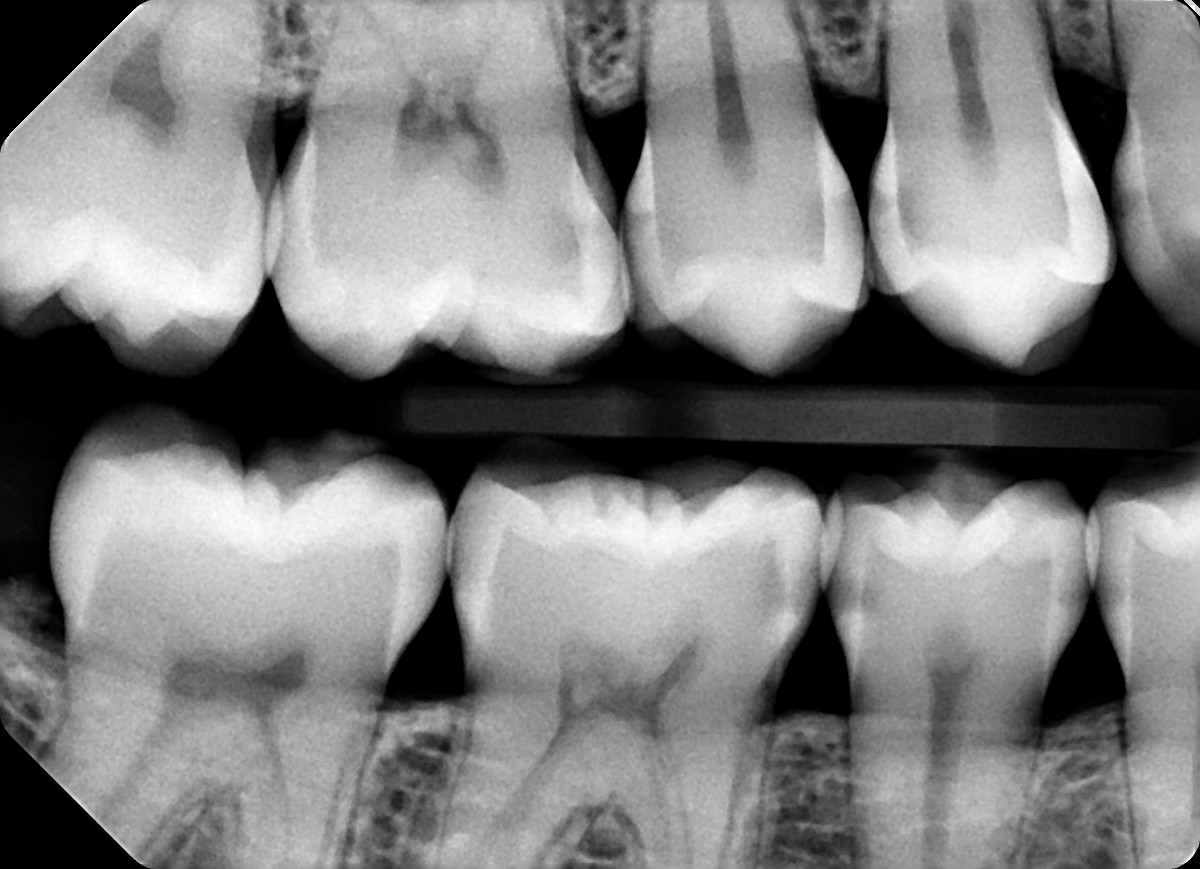

3. In the X ray bellow for which jaw periodontal bone loss is evident?